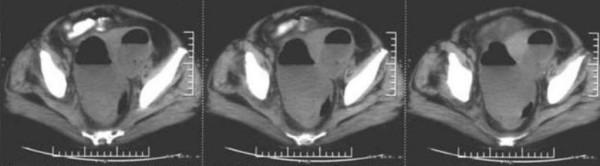

本报告描述了一名72岁女性,有1个月的非血性腹泻、腹痛和低热病史。计算机断层扫描证实盆腔区域存在一个大的局部气液平面。剖腹手术发现一个大的盆腔脓肿,位于直肠乙状结肠和子宫之间,直肠乙状结肠和子宫有严重的组织坏死。